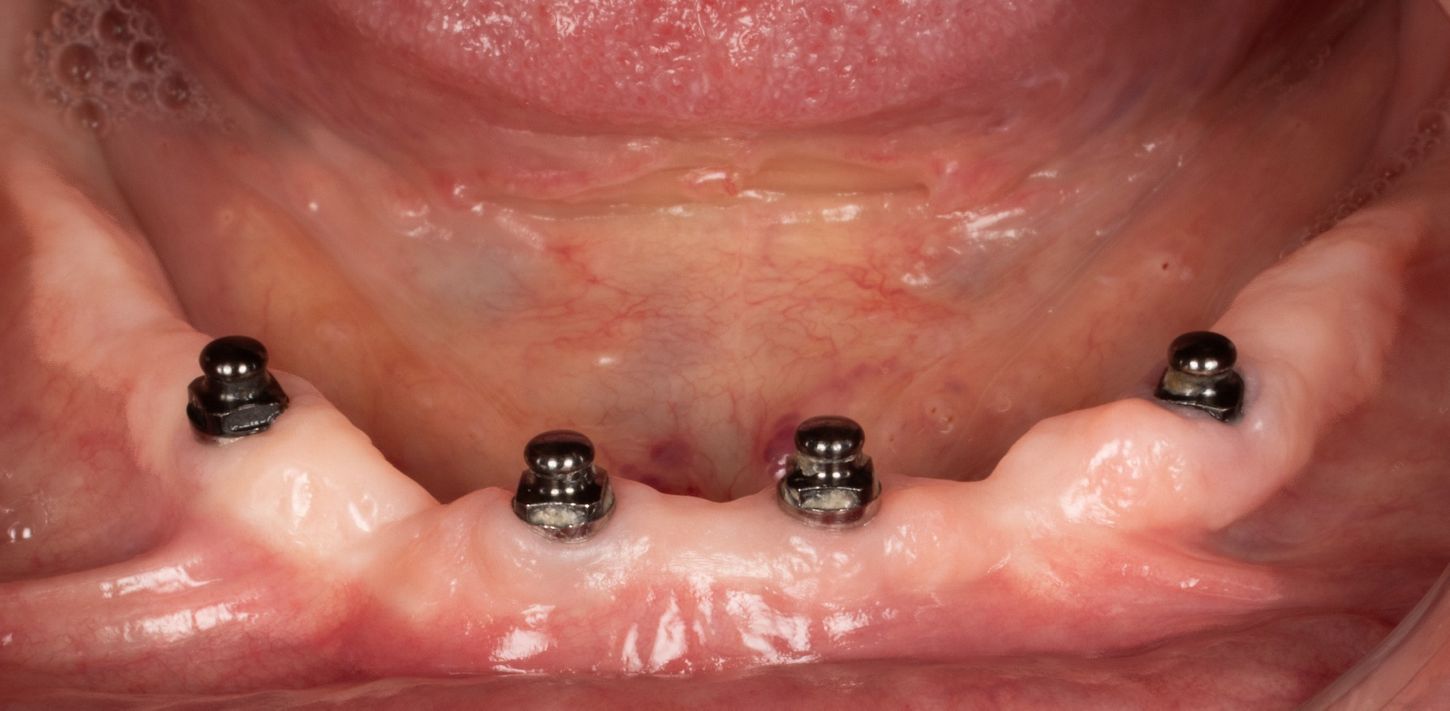

7a. 7b. Post-operative view of the complete removable prosthesis immediately secured to the mini implants with Optiloc connectors.

The post-operative instructions given were a soft diet for 15 days with no removal of the prosthesis during this initial healing phase. The patient was prescribed level 1 painkillers and mouthwash).

7a

7b